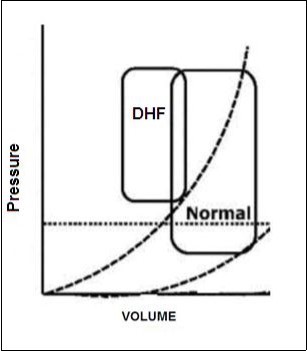

Although each cell type and heart Chamber can potentially be involved in the beginning of the HF, there is often to top left ventricular (LV) dysfunction linked to a lifting of the pressures of filling of the LV3, 5, 6 (Diastolic Disfunction).Figure 1.

Figure 1.Deflection curve of volume/pressure ratio in heart failure by diastolic

In the last decade it has been described that when the LV ejection fraction (EF) is reduced (≤40%), is a condition called "systolic dysfunction", what defines the IC as "IC with reduced ejection fraction" (HFrEF). When LVEF is ≥50%, but have concomitant impaired relaxation of the left ventricle, a condition called "diastolic dysfunction", along with the presence of pathognomonic signs and symptoms of IC, is classified as "IC with preserved ejection fraction" (HFpEF).

Individuals with heart failure and a faith between 40% and 50% are considered as part of an intermediate group (gray area), situation which we have also known as HF with systolic dysfunction in transit3. In addition, LV diastolic dysfunction may also be present in the own HFrEF4Interestingly, HFrEF and HFpEF may be differentiated according to the phenotype of the patient. HFpEF subjects, compared with HFrEF, are often older women, with a higher body mass index, increased prevalence of diabetes, atrial fibrillation and a history of high blood pressure5. The estimated prevalence of HFpEF among subjects with IC is approximately 50%6, 7. So is today already recognized as pandemic, by its close relationship with factors of cardiovascular risk such as hypertension, diabetes, Dyslipidemia, obesity, COPD and sleep apnea.

HFpEF, LV cavity typically has a normal volume and the walls are hypertrophic. See Figure 2. Histological examination shows the deposition of collagen and cardiomyocytes larger, stiffer than in HFrEF4. Despite the different cardiac structure and function, HFrEF and HFpEF hemodynamic patterns share similarities as well as differences. The clinical symptoms, renal dysfunction, neurohormonal activation, response to exercise and clinical findings may overlap10 However, increased ventricular and vascular stiffness can play a greater role than a real volume overload, in HFpEF compared with HFrEF. Thus, these two forms of IC are two well differentiated entities, with different pathophysiology and therapeutic approaches accordingly.